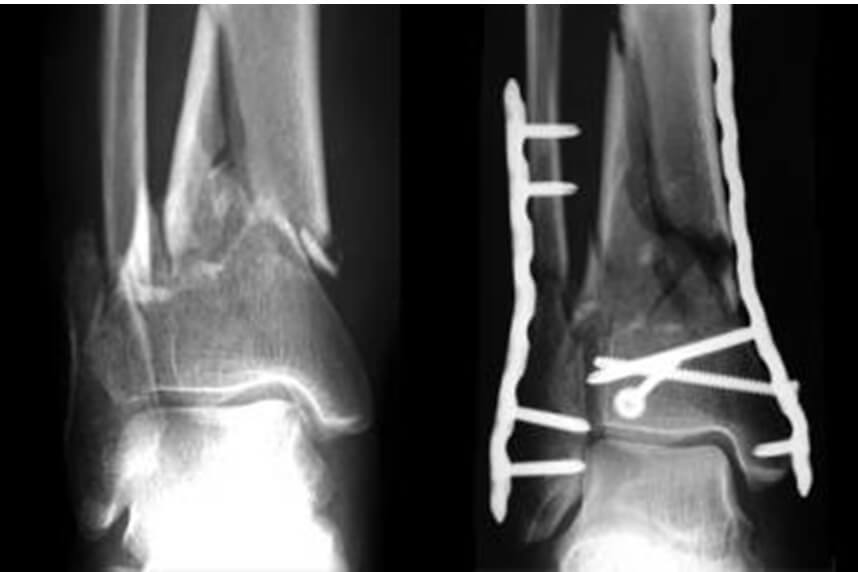

Fractura de tibie sau peroneu (fibula)

![]()

Tratamentul de urgenta pentru fracturi la nivelul tibiei sau peroneului (fibulei) este acordat de medicul specialist in cadrul primului ajutor. Acesta va hotari daca este nevoie de o reducere a fracturii sau de o fixare chirurgicala de catre un medic chirurg ortoped. Dupa acestea este foarte important sa se inceapa un program kinetoterapeutic precoce, personalizat imediat dupa externare.